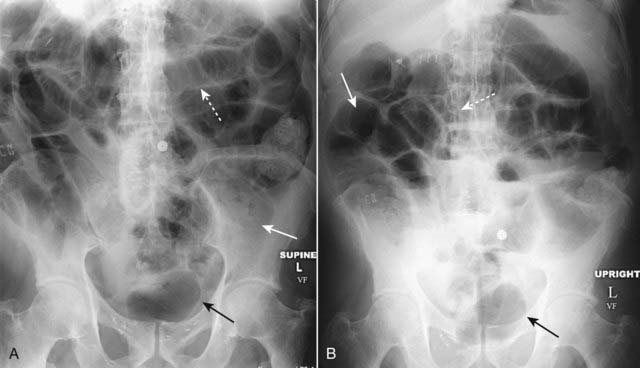

Figure 14-2 Generalized adynamic ileus, supine (A) and upright abdomen (B).

There are dilated loops of large (solid white arrows) and small bowel (dotted white arrows) with gas seen down to and including the rectum (solid black arrows). The patient had undergone colon surgery the previous day.